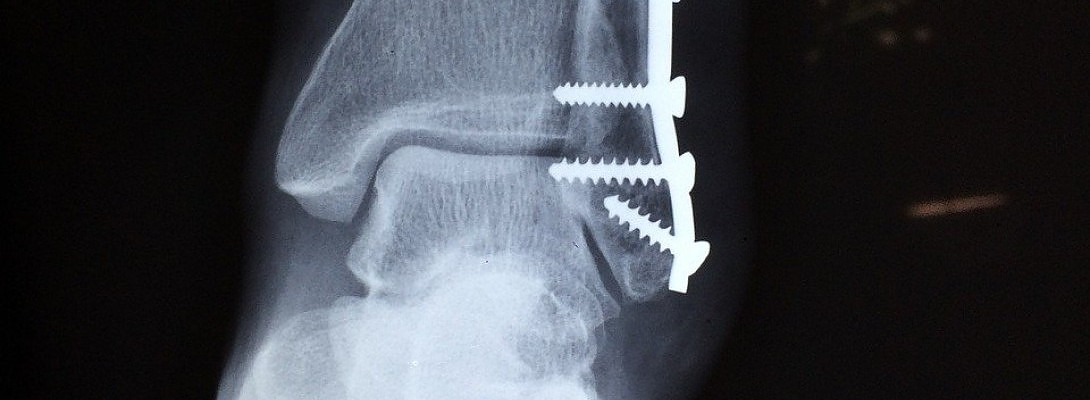

So I went to the doctor today and found out that I don't have to come back for three months and no more x-rays. My bone is growing back perfectly now.